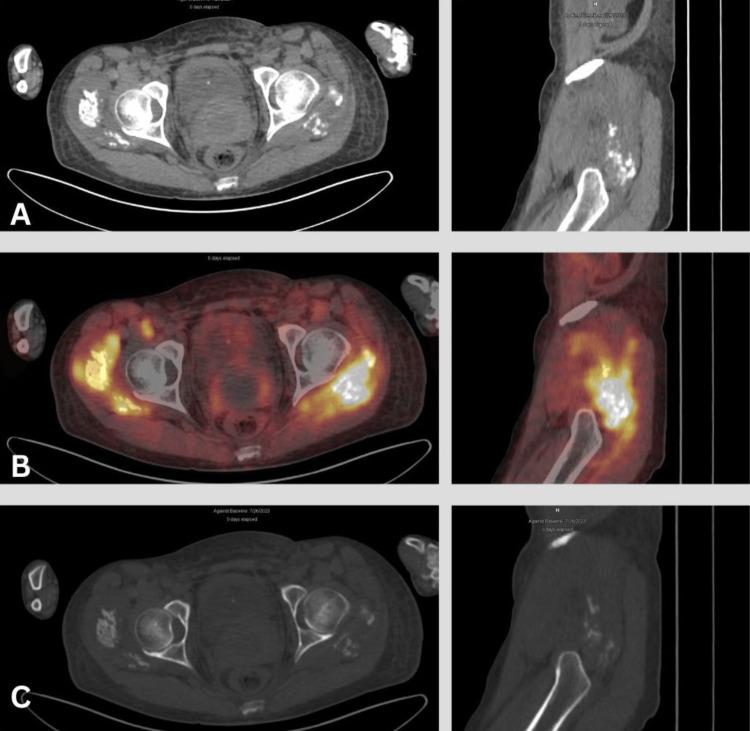

Positron emission tomography/computed tomography (PET/CT) using 18F-fluorodeoxyglucose ([18F]-FDG) is a widely adopted imaging modality for detecting hypermetabolic lesions. However, emerging positron-emitting tracers, such as radiopharmaceuticals featuring fibroblast activation protein (FAP) inhibitors (FAPI) labeled with [18F] or [68Ga], have opened new avenues in nuclear medicine. This case report focuses on the unique behavior of [68Ga]-FAPI in bilateral gluteal myositis ossificans, an infrequent condition characterized by soft tissue ossification. A 45-year-old woman with gastric adenocarcinoma underwent subtotal gastrectomy and received neoadjuvant and adjuvant chemotherapy; [68Ga]-FAPI PET revealed metastatic processes and unexpected [68Ga]-FAPI avid intramuscular ossifications in the pelvic and bilateral thigh muscles. Even though there was no history of trauma, the patient was diagnosed with myositis ossificans, a condition marked by non-cancerous ectopic ossifications. Diagnosis relies on history, radiology, and/or histology. FAPI imaging, increasingly used for inflammatory and infectious diseases, can exhibit uptake in benign conditions, including those involving bones and joints. This case report is the first to document incidental bilateral [68Ga]-FAPI uptake in bilateral gluteal myositis ossificans. The robust [68Ga]-FAPI activity in myositis ossificans highlights the importance of considering myositis ossificans in the context of soft tissue calcifications with intense [68Ga]-FAPI uptake.

使用18F-氟脱氧葡萄糖([18F]-FDG)的正电子发射断层扫描/计算机断层扫描(PET/CT)是一种广泛应用于检测高代谢病变的成像方式。然而,新出现的正电子发射示踪剂,如标记有[18F]或[68Ga]的成纤维细胞活化蛋白(FAP)抑制剂(FAPI)的放射性药物,为核医学开辟了新途径。本病例报告重点关注[68Ga]-FAPI在双侧臀肌骨化性肌炎中的独特表现,这是一种以软组织骨化为特征的罕见病症。一名45岁的胃腺癌女性患者接受了胃大部切除术,并接受了新辅助和辅助化疗;[68Ga]-FAPI PET显示有转移过程以及盆腔和双侧大腿肌肉中出现意外的[68Ga]-FAPI摄取增加的肌内骨化。尽管没有创伤史,但该患者被诊断为骨化性肌炎,这是一种以非癌性异位骨化为特征的病症。诊断依赖于病史、放射学和/或组织学检查。FAPI成像越来越多地用于炎症和感染性疾病,在包括涉及骨骼和关节的良性病症中也可表现出摄取增加。本病例报告首次记录了双侧臀肌骨化性肌炎中偶然出现的双侧[68Ga]-FAPI摄取。骨化性肌炎中强烈的[68Ga]-FAPI活性突出了在具有强烈[68Ga]-FAPI摄取的软组织钙化情况下考虑骨化性肌炎的重要性。